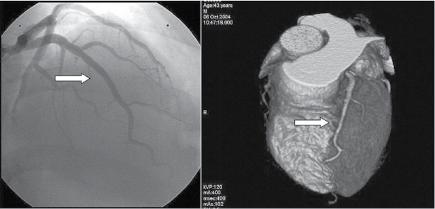

Figure 1.1 (A) Normal case: coronary angiography (left) and three‐dimensional CTA (right) showing normal left anterior descending (LAD, arrow) and left circumflex (LCX) coronary arteries. The latter is partially covered by the left appendix in CTA. (B) Normal case: coronary angiography (left) and CTA (right) showing a normal dominant right coronary artery (RCA). (C) An 85‐year‐old man with atypical chest pain: (a) Maximal intensity projection (MIP) of CTA with tight mid‐LAD stenosis that correlates perfectly with coronary angiography (b). (D) Similar case as (C) but with the stenosis in the proximal RCA. (a–d) CTA and (e) coronary angiography. (E) A patient with tight stenosis in the LCX before a bifurcation. (a) and (b) CTA and (c) coronary angiography. (F) These images show that CTA may also demonstrate the presence of stenosis in distal vessel branches, in this case in the posterior descending branch of the RCA. (a–b) CTA and (c) coronary angiography. (G) These images show that CTA (a, b) may delineate the length of a total occlusion and visualize the distal branches (see arrows in (b)). Collateral flow from the LAD to the RCA may be better visualized with CTA than with conventional coronary angiography (c: here only the RCA is shown). (H) A 42‐year‐old patient with a stent implanted in the LAD six months before. The patient complained of atypical chest pain and underwent CTA. The MIP images of CTA (a–c) show no significant restenosis, but some plaque formation in the left main trunk (d, circle) that was not well seen in coronary angiography (e). The degree of luminal obstruction by the plaque can be exactly measured by intravascular ultrasound (IVUS) (f). The ECG showed mildly inverted T waves in V1–V3 during follow‐up (see Plate 1 in color plates).

intervention (PCI) (Figure 1.1). CTA may provide additional diagnostic information for clinical decision‐making in contemporary stable chest pain patients with intermediate pre‐test probability for IHD (Hoffmann et al. 2017). In additional to narrowing, CTA can provide information on coronary distribution, including abnormalities in the origin and course of the arteries, and presence of coronary aneurysms. However, the accuracy of assessing the severity of coronary stenosis in highly calcified lesions and within stents is reduced.